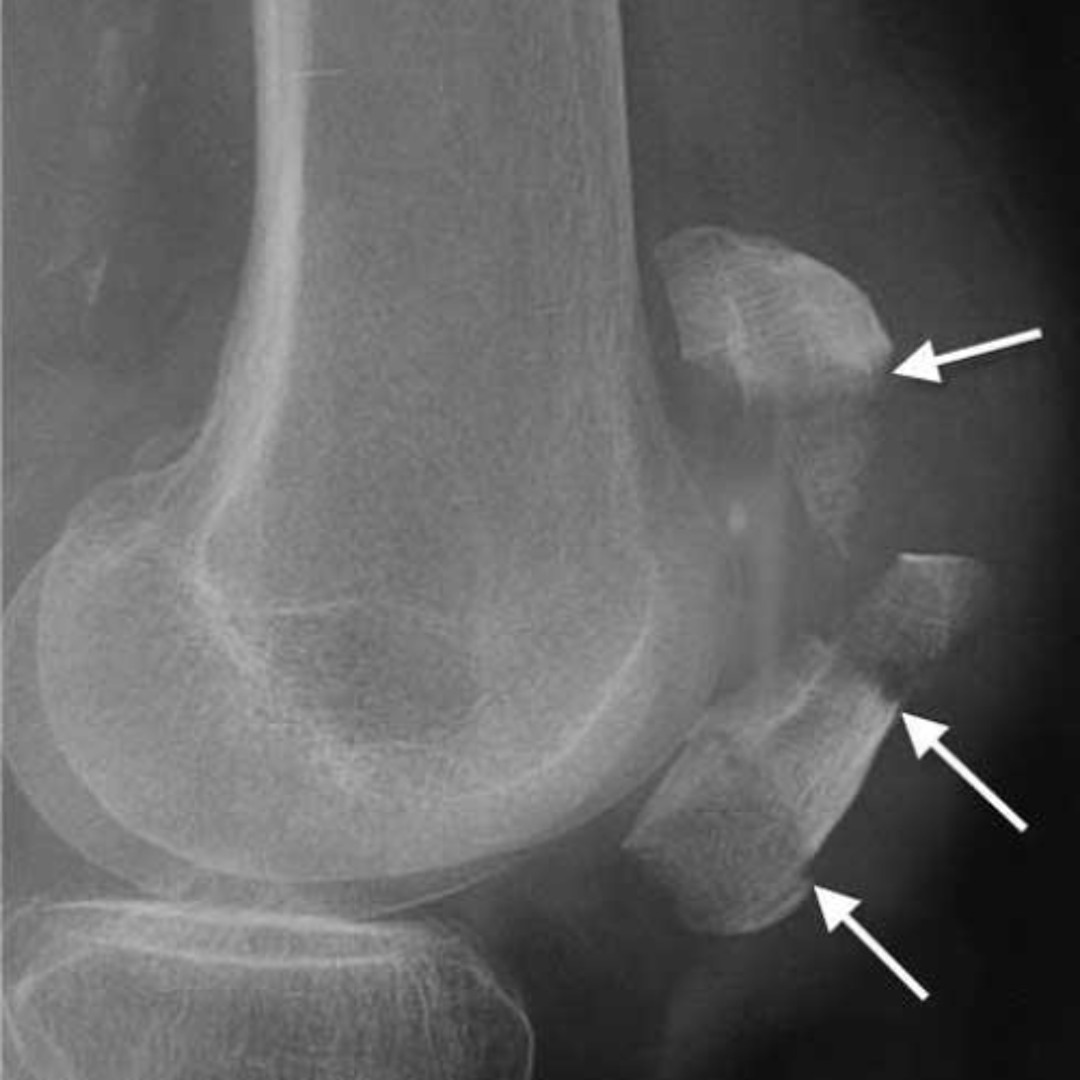

Надколенник смещен

Надколенник смещен 116 фото